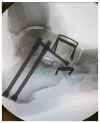

Background: Continuous Compression Implants (CCIs) are low-profile implants made of nitinol and titanium. They offer multiple benefits in comparison to plate and screw fixation for foot and ankle indications, and they are designed in such a way that they continuously and dynamically compress the opposed bony surfaces throughout the entire healing process. Methods: In this study, we present our experience on the use of those nitinol implants for midfoot and hindfoot surgery. Furthermore, we elaborate on the advantages and downsides of using this internal fixation method and highlight common pitfalls which could lead to undesirable clinical outcomes. We also demonstrate our proposed surgical technique on how to use CCIs in a reproducible and reliable way and present surgical tips which could help reduce surgical time when utilising these implants. We also make surgical recommendations on their use and present the underlying biomechanics, which could provide a better understanding of the rationale behind using them in the field of foot and ankle surgery. Last but not least, we presented the early clinical and radiological results of a series of patients who underwent primary midfoot fusion for Lisfranc injury between 2020 and 2023. Results: With a minimum follow-up of 9 months, satisfactory clinical and radiological union was noted in all those patients. The mean difference between pre- and post-operative MOxFQ scores was -37.7 (95% CI was 16.9 to 58.5; p = 0.03). The mean post-operative VAS pain at rest was 3.2 (SD = 2.3). No major complications were noted. Conclusions: CCI internal fixation is a safe, reproducible, and reliable method when it comes to foot and ankle conditions, but it requires appropriate pre-operative planning, surgical training, and careful implantation.